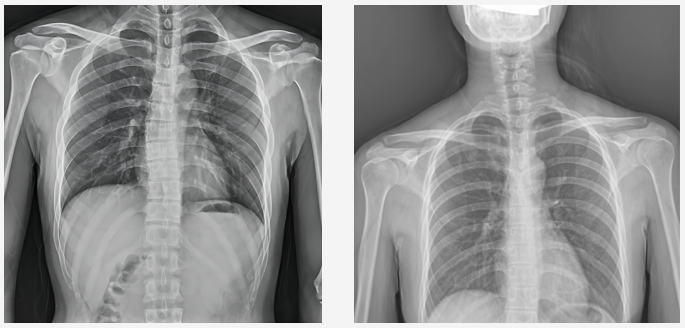

普愛動態DR臨床圖像

DR圖像質量對比圖

當前國產DR都尤其重視圖像后處理系統的升級,如普愛醫療研發生產的多功能動態DR(型號:PLX8100),應用了公司自主研發的組織均衡技術,它是基于低灰度區擴展到高灰度區間的多層分級細節均衡算法。對于人體圖像,通過組織均衡后,圖像細節突出明顯,肺紋理末端細小血管及骨骼的紋理、肌肉層次等均可清晰顯示。